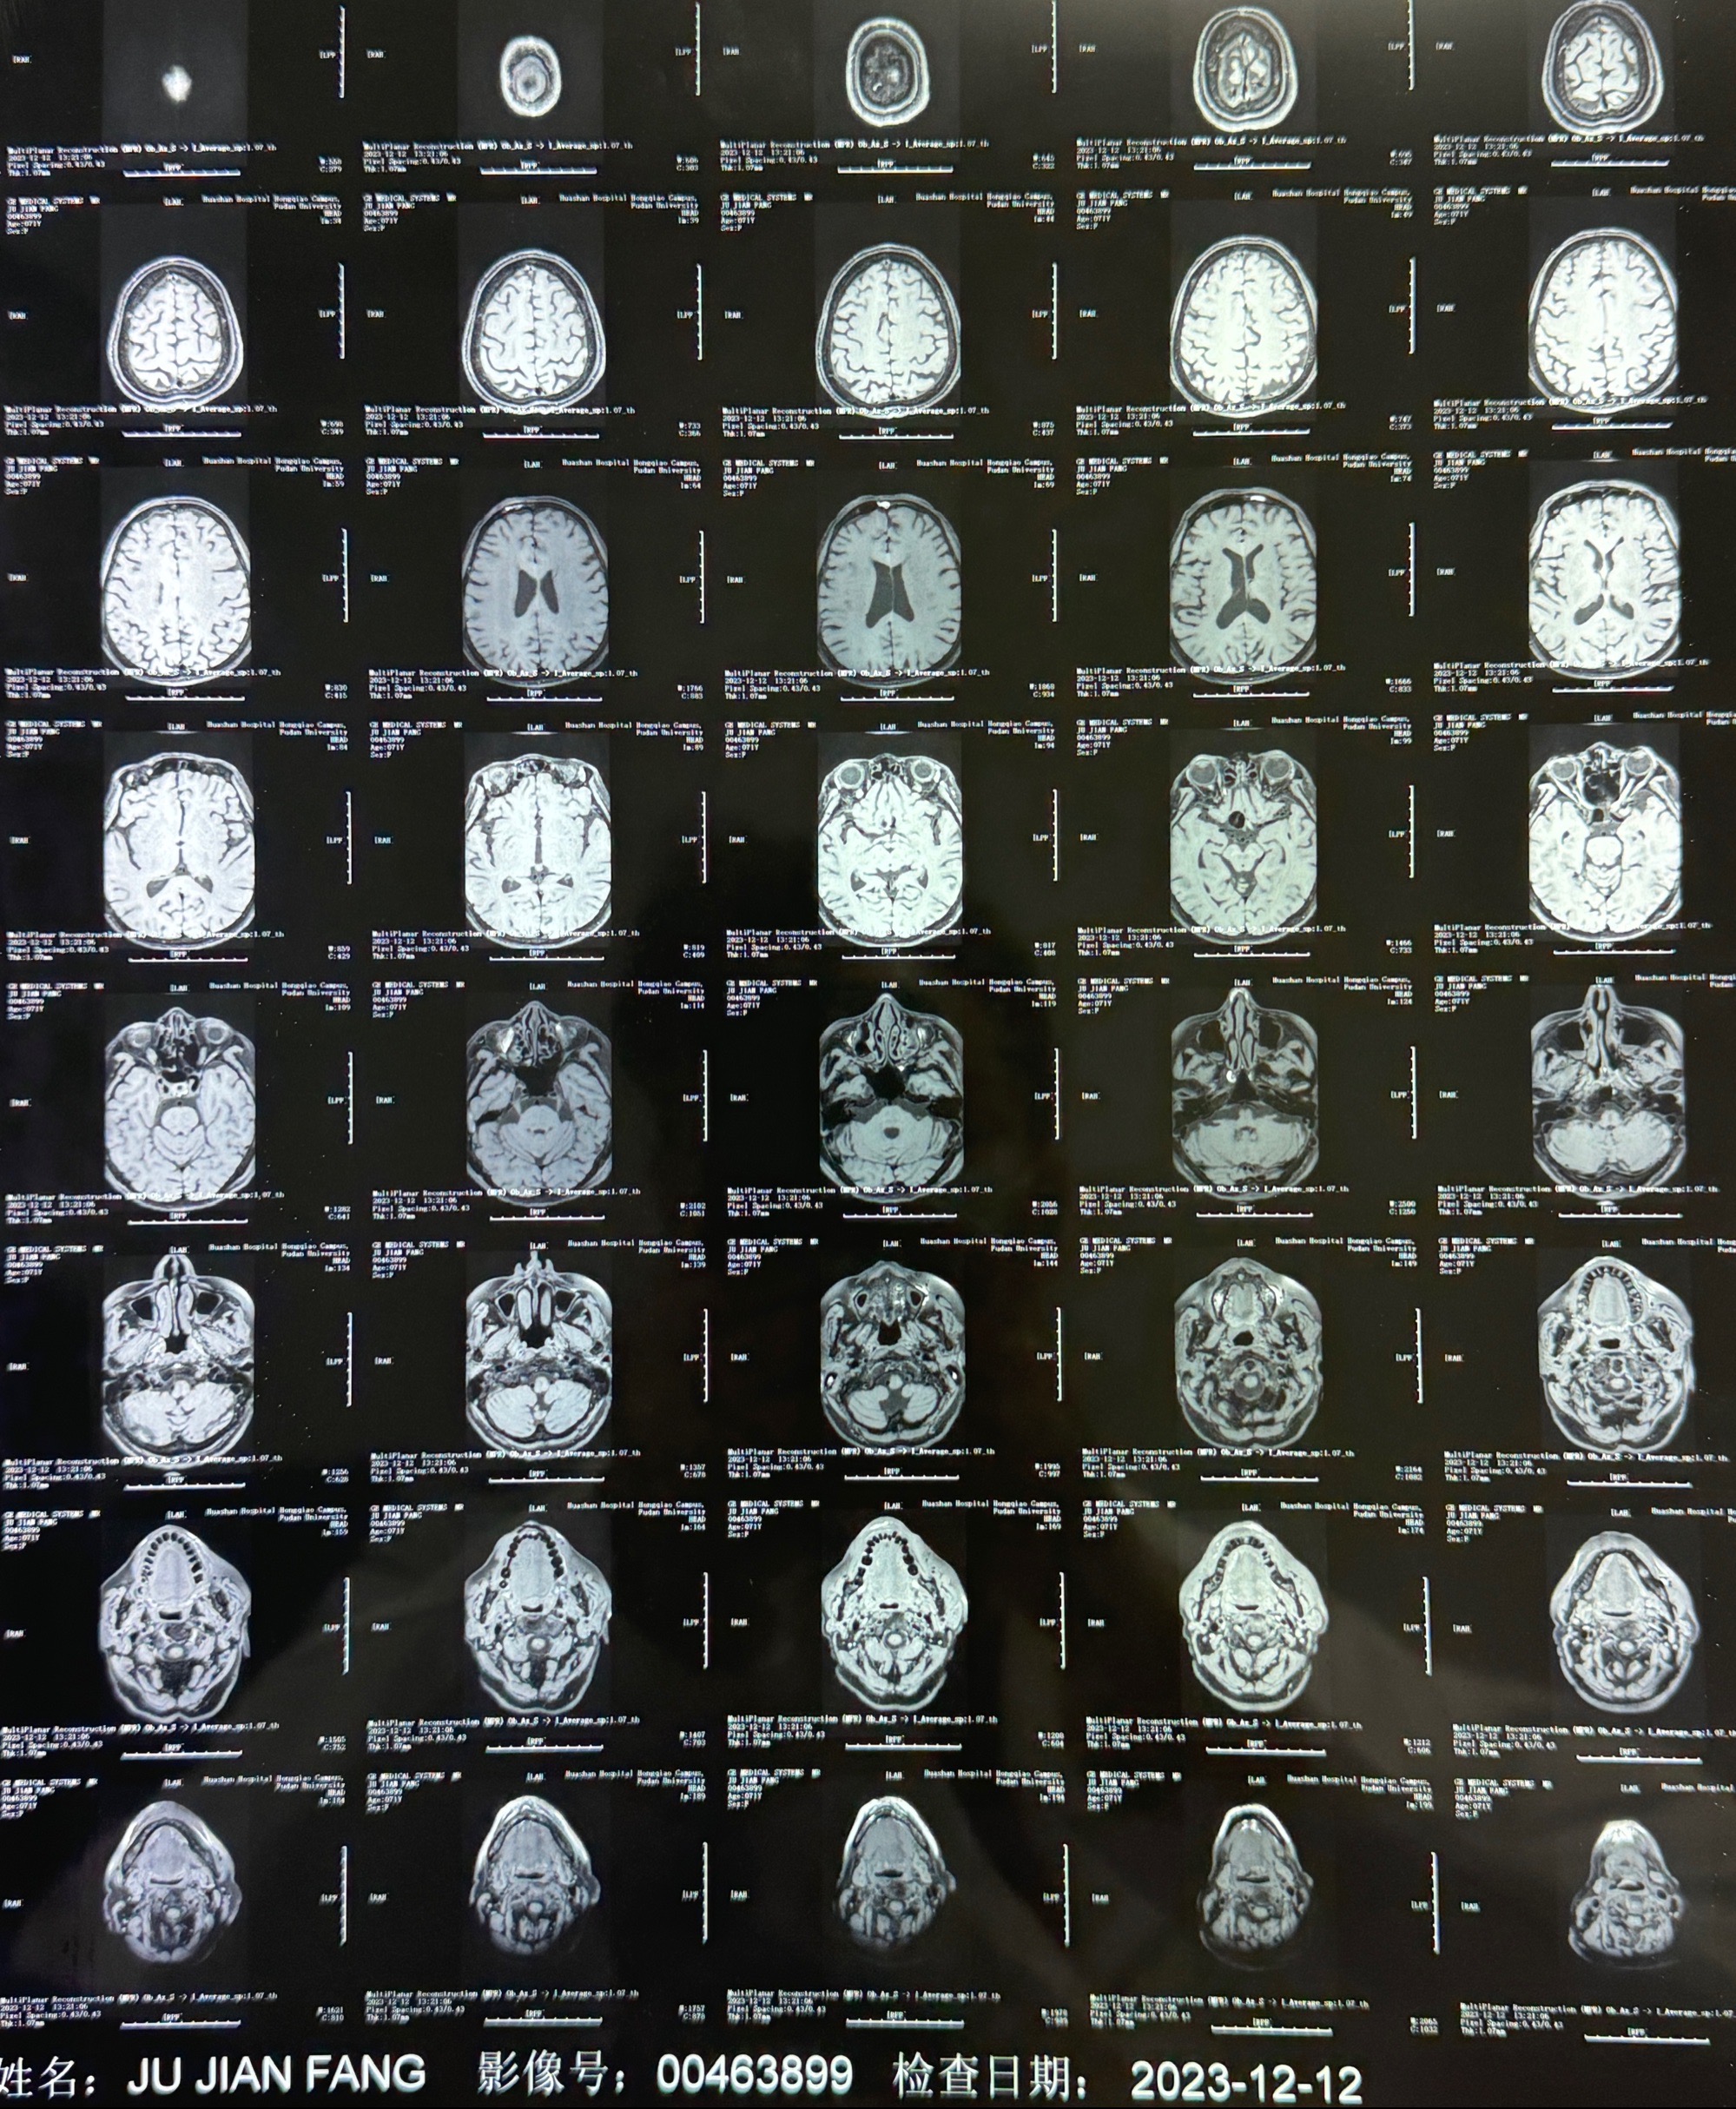

2023-12-12MRI